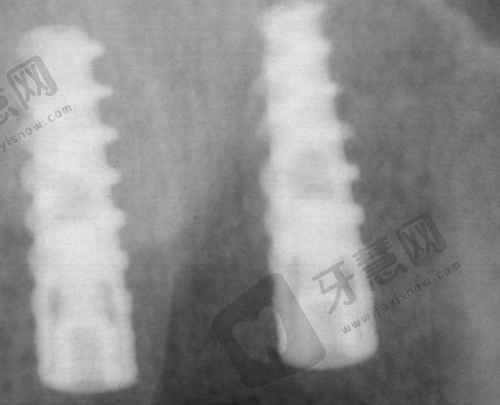

口腔种植优势:口腔种植项目中,使用的种植体质量可靠,医生种植技术不错,能确保种植的成功几率与稳定性。